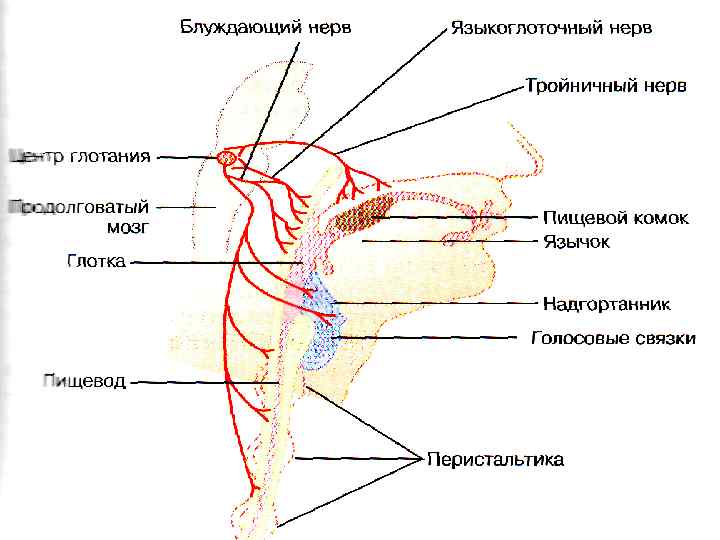

ФАЗЫ ГЛОТАНИЯ РОТОВАЯ (ПРОИЗВОЛЬНАЯ) ГЛОТОЧНАЯ ПИЩЕВОДНАЯ

ФАЗЫ ГЛОТАНИЯ РОТОВАЯ (ПРОИЗВОЛЬНАЯ) ГЛОТОЧНАЯ ПИЩЕВОДНАЯ

ГЛОТОЧНАЯ ФАЗА

ГЛОТОЧНАЯ ФАЗА

1. МЯГКОЕ НЕБО ЗАКРЫВАЕТ ХОАНЫ 2. НЕБНО-ГЛОТОЧНЫЕ СКЛАДКИ – САГИТТАЛЬНУЮ ЩЕЛЬ 3. ГОЛОСОВАЯ ЩЕЛЬ СМЫКАЕТСЯ, ГОРТАНЬ ПОДТЯГИВАЕТСЯ ВВЕРХ → НАДГОРТАННИК – КЗАДИ

1. МЯГКОЕ НЕБО ЗАКРЫВАЕТ ХОАНЫ 2. НЕБНО-ГЛОТОЧНЫЕ СКЛАДКИ – САГИТТАЛЬНУЮ ЩЕЛЬ 3. ГОЛОСОВАЯ ЩЕЛЬ СМЫКАЕТСЯ, ГОРТАНЬ ПОДТЯГИВАЕТСЯ ВВЕРХ → НАДГОРТАННИК – КЗАДИ

4. ПИЩЕВОД – ВВЕРХ, ВХОД РАСШИРЯЕТСЯ 5. ВЕРХНИЙ ПИЩЕВОДНЫЙ СФИНКТЕР РАСКРЫВАЕТСЯ 6. ГЛОТКА СОКРАЩАЕТСЯ, ПРОТАЛКИВАЯ ПИЩУ t=2 c

4. ПИЩЕВОД – ВВЕРХ, ВХОД РАСШИРЯЕТСЯ 5. ВЕРХНИЙ ПИЩЕВОДНЫЙ СФИНКТЕР РАСКРЫВАЕТСЯ 6. ГЛОТКА СОКРАЩАЕТСЯ, ПРОТАЛКИВАЯ ПИЩУ t=2 c

РЕГУЛЯЦИЯ ГЛОТАНИЯ

РЕГУЛЯЦИЯ ГЛОТАНИЯ

ЗАДНЯЯ ОБЛАСТЬ ЗЕВА И ГЛОТКИ → чувствительные волокна V и IX → NTS → двигательные волокна V, IX, X и XII trigeminus, glossopharyngeus, vagus, hypoglossus

ЗАДНЯЯ ОБЛАСТЬ ЗЕВА И ГЛОТКИ → чувствительные волокна V и IX → NTS → двигательные волокна V, IX, X и XII trigeminus, glossopharyngeus, vagus, hypoglossus

ВЕРХНЯЯ 1/3 – СКЕЛЕТНЫЕ МЫШЦЫ (СОМАТИЧЕСКИЕ НЕРВЫ) НИЖНИЕ 2/3 – ГЛАДКИЕ МЫШЦЫ (ВАГУС)

ВЕРХНЯЯ 1/3 – СКЕЛЕТНЫЕ МЫШЦЫ (СОМАТИЧЕСКИЕ НЕРВЫ) НИЖНИЕ 2/3 – ГЛАДКИЕ МЫШЦЫ (ВАГУС)

X IX V

X IX V

ЦЕНТР ГЛОТАНИЯ на 2 -6 с ПОДАВЛЯЕТ ДЫХАТЕЛЬНЫЙ ЦЕНТР

ЦЕНТР ГЛОТАНИЯ на 2 -6 с ПОДАВЛЯЕТ ДЫХАТЕЛЬНЫЙ ЦЕНТР